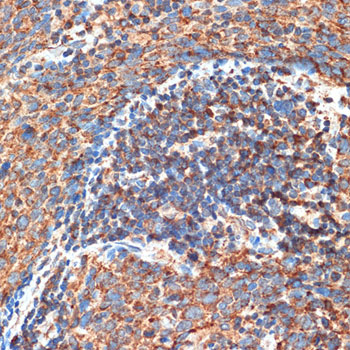

Immunohistochemistry of paraffin-embedded human esophageal cancer using FIP200 Rabbit pAb.